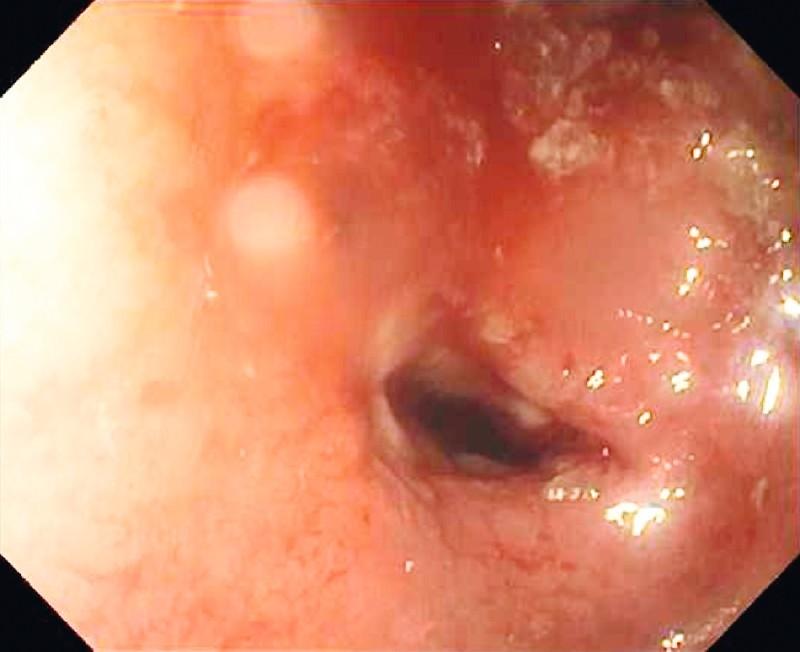

In total, 78 BAE procedures were carried out in 65 patients. In group A (n = 22, 25 BAE procedures), enteroscopy led to a diagnosis of CD in six patients (27.3 %). Non-steroidal anti-inflammatory drug-related enteropathy was diagnosed in three patients (13.6 %), whereas no lesions were found in the remaining 13 patients. In group B (n = 43, 53 BAE procedures) enteroscopy revealed active intestinal inflammation with ulcers and/or luminal stenosis in 18 patients (41.9 %), which led to a change and escalation of medical therapy. Five patients without active ulcers underwent successful dilation of small-bowel strictures with resulting resolution of obstructive symptoms. Of the 78 BAE procedures, two patients (2.6 %) had bleeding complications which were successfully treated conservatively. One patient (1.3 %) underwent surgery due to procedure-related perforation.

65例患者共进行了78次BAE检查。在A组(n = 22,25次BAE检查)中,小肠镜检查确诊6例CD患者(27.3%)。3例患者(13.6%)被诊断为非甾体抗炎药相关性肠病,其余13例患者未发现病变。在B组(n = 43,53次BAE检查)中,小肠镜检查发现18例患者(41.9%)有伴有溃疡和/或管腔狭窄的活动性肠道炎症,这导致了药物治疗的改变和升级。5例无活动性溃疡的患者成功扩张了小肠狭窄,梗阻症状得以缓解。在78次BAE检查中,2例患者(2.6%)出现出血并发症,经保守治疗成功。1例患者(1.3%)因检查相关穿孔接受了手术。